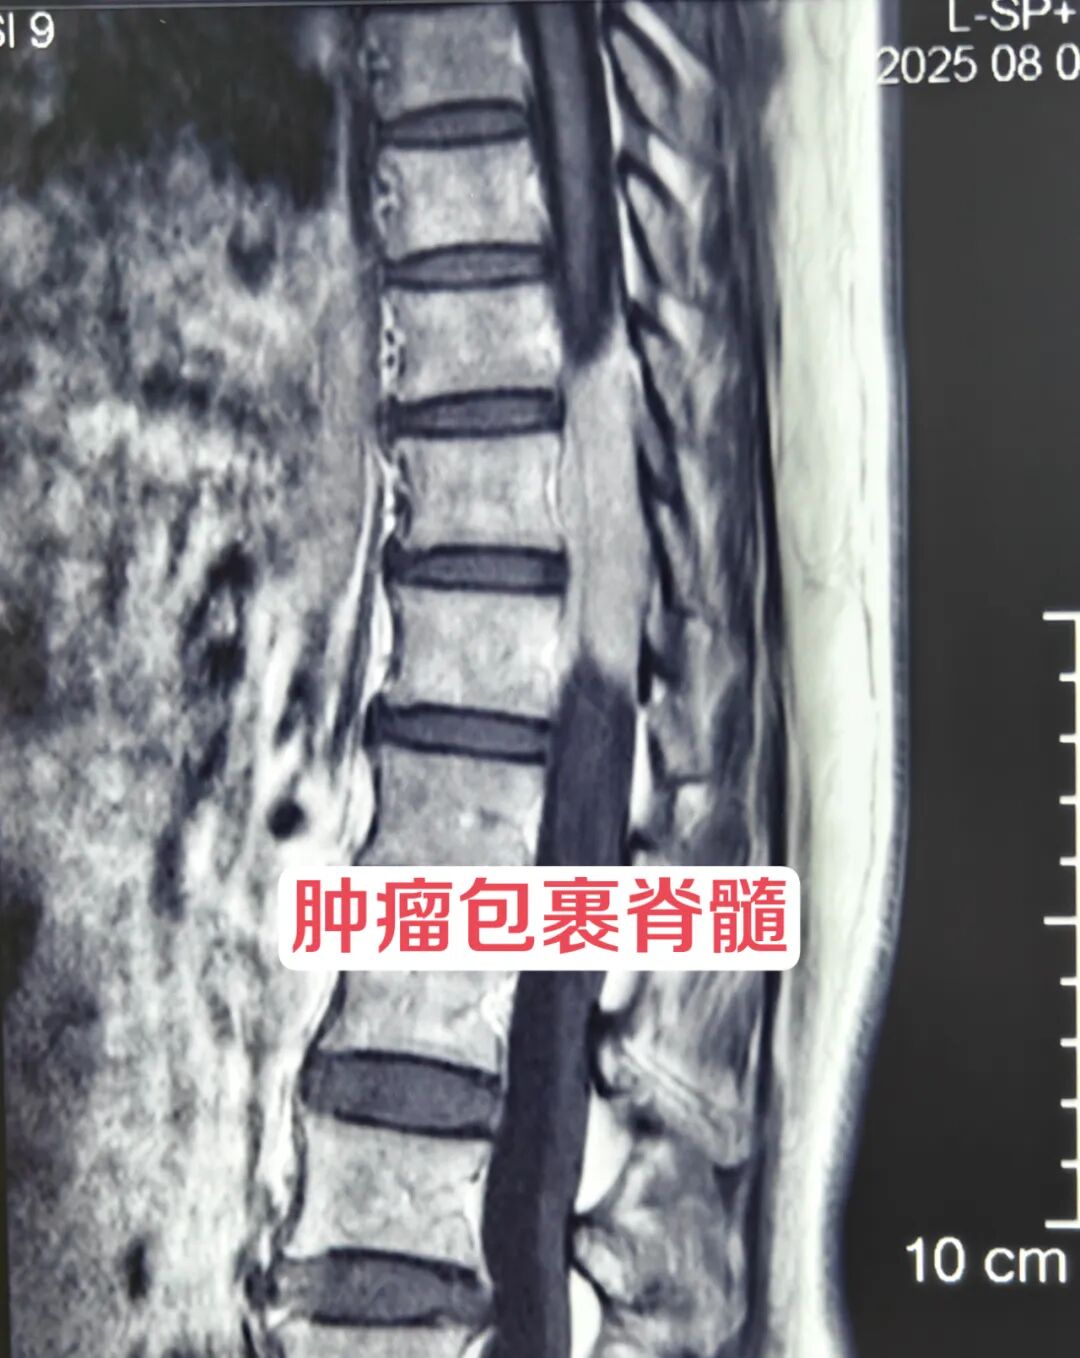

患者女,53岁,主因“胸腰背部疼痛不适1年加重伴双下肢无力2月”入院。患者1年前开始出现胸腰背部疼痛,以为是腰肌劳损,自行按摩理疗稍缓解后就没再理会。近两月来,患者疼痛进行性加重,疼痛评分8分,已严重影响行走,来院时已无法独立行走,需搀扶行走,行走似踩棉花感,大便便秘,小便费力。入院查体提示下肢肌力3级,病理征阳性。磁共振提示胸腰段巨大肿瘤包裹脊髓,且血供丰富。经过西安市红会医院神经外科赵东升主任仔细阅片分析病情后,决定手术切除肿瘤。

术前增强磁共振

术中见肿瘤包裹脊髓且向脊髓腹侧及椎间孔生长,赵主任在显微镜下仔细将肿瘤从脊髓剥离并切除,并沿神经根探查将包裹神经根的肿瘤一并切除。

术后患者疼痛立即消失,下肢自主活动,术后复查磁共振提示肿瘤全切。